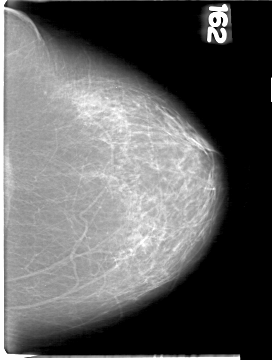

D_4094_1.LEFT_CC

LEFT_CC LINES 5386 PIXELS_PER_LINE 4066 BITS_PER_PIXEL 12 RESOLUTION 43.5 NON_OVERLAY

FILE: D_4094_1.RIGHT_CC.OVERLAY

TOTAL_ABNORMALITIES 1

ABNORMALITY 1

LESION_TYPE MASS SHAPE ROUND MARGINS OBSCURED

ASSESSMENT 0

SUBTLETY 4

PATHOLOGY BENIGN

TOTAL_OUTLINES 1

BOUNDARY